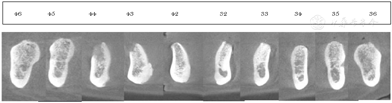

种植修复后1、2、4年随访X线全颌曲面体层片显示种植体周围骨结合良好(图13A~C),患者对修复体美观及咀嚼功能效果满意。修复后6年(2022年8月)随访X线全颌曲面体层片及根尖片显示种植体周骨结合良好,上前牙区种植体颈部骨吸收约1 mm(图13D、图14)。取下上下颌义齿,清理义齿组织面滞留菌斑,清洁复合基台并检查基台中央螺丝稳定,清洁义齿组织面,戴回上下颌义齿(图15)。患者口腔卫生宣教,指导正确刷牙,使用冲牙器冲洗义齿与牙龈间缝隙,嘱6个月复查、维护。